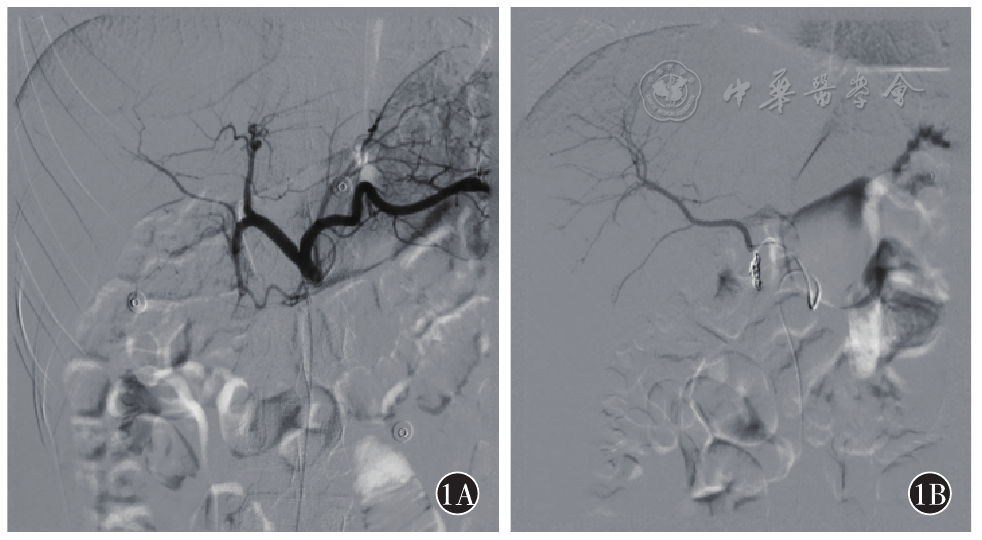

图1 腹腔干造影及胃十二指肠动脉栓塞